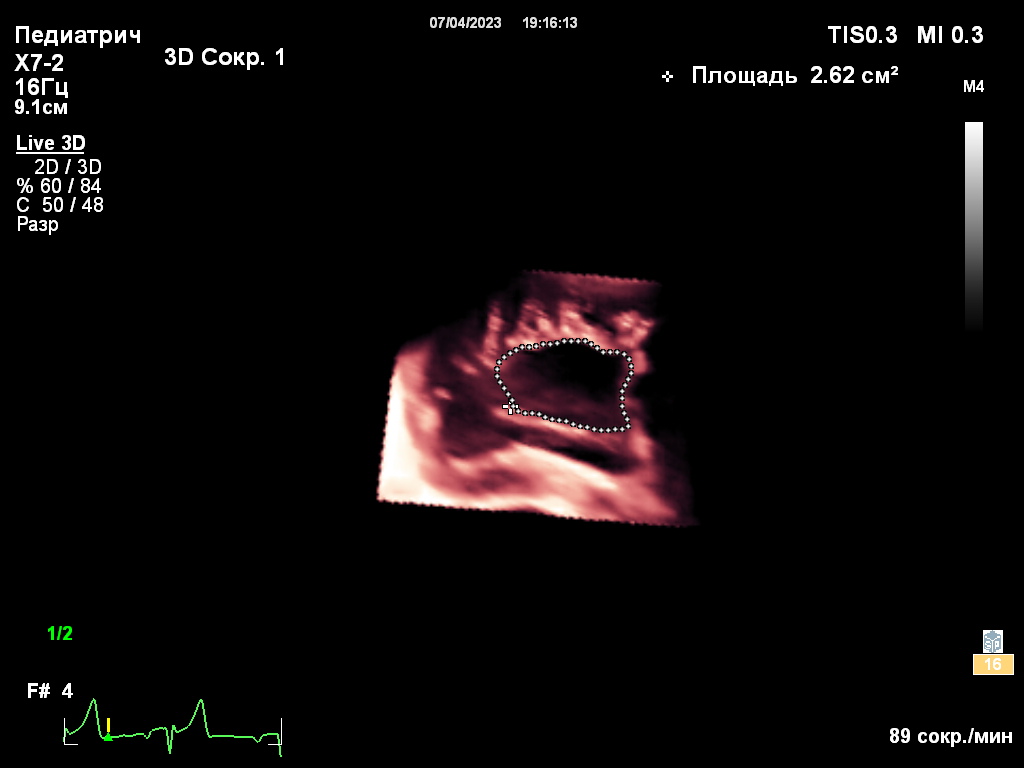

Собака находилась под наблюдением с 5-месячного возраста. При эхокардиографическом исследовании были выявлены следующие аномалии (фото 1-3):

- Выраженная дилатация правого предсердия (47 мм) и правого желудочка (конечный диастолический размер – 34 мм).

- Неделаминированная и малоподвижная септальная створка.

- Укороченные хорды.

- Выраженная регургитация (massive).

- Гепатомегалия, обусловленная застоем крови в системных венах.